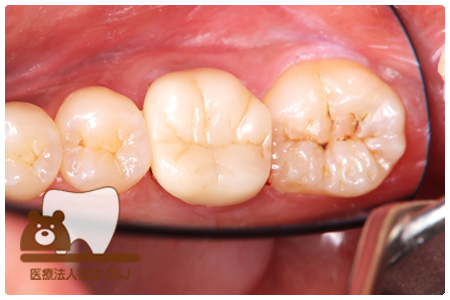

症例7フルジルコニアクラウン

治療前

治療後

43歳 女性

- 治療内容

- 虫歯で大きく失われた歯に対して、土台としてファイバーコアを使用し、その上にフルジルコニア製の被せ物を装着しました。見た目と強度を両立した自由診療の治療です。

- 治療期間

- 5カ月

- 費用

- 自費

フルジルコニアクラウン:77,000円(税込)(R7.12月現在)

- その他の治療の費用は含まれておりません。

- リスク・副作用

- 硬い素材のため、かみ合う歯に負担がかかることがあります。将来取り外す場合に歯に負担がかかることがあります。強い力が加わると、まれに欠けたり割れたりすることがあります。